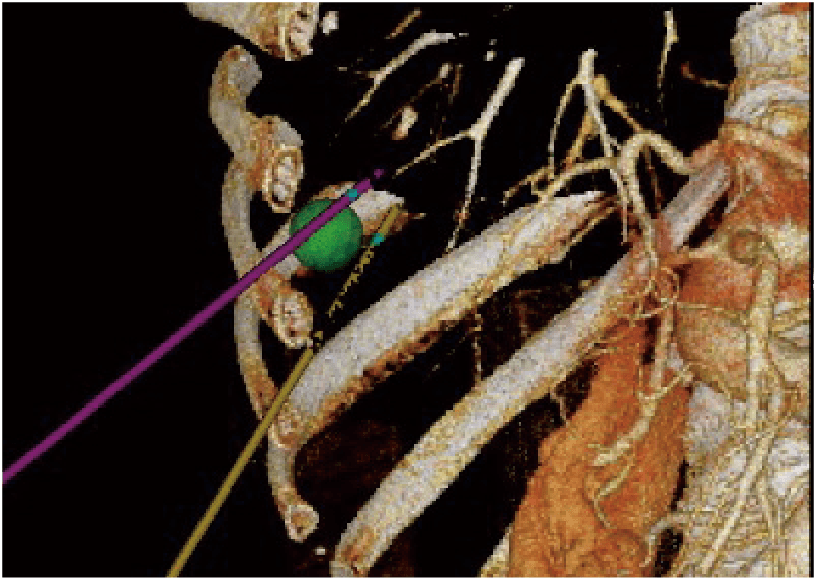

Provides simulation of single or multiple needle paths during navigation to a target with Real-time Virtual Sonography (RVS). The positional relationship between the marked target and needle paths can be assessed in real time using the 3D body mark and C-plane display. E-field Simulator superimposes the electric field (E-field) from the given location of electrodes on the CT image during RFA treatment. The simulation of E-field allows to consider an effective needle path.